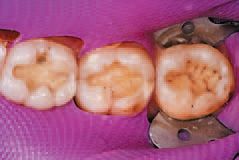

After inspecting the old amalgam restorations (Fig. 2), a rubber dam was then placed (Fig. 3). Next, using Sybron Dental’s Axis course diamond bur, KS3, the amalgam restorations and all damaged tooth structure were removed (Fig. 4).